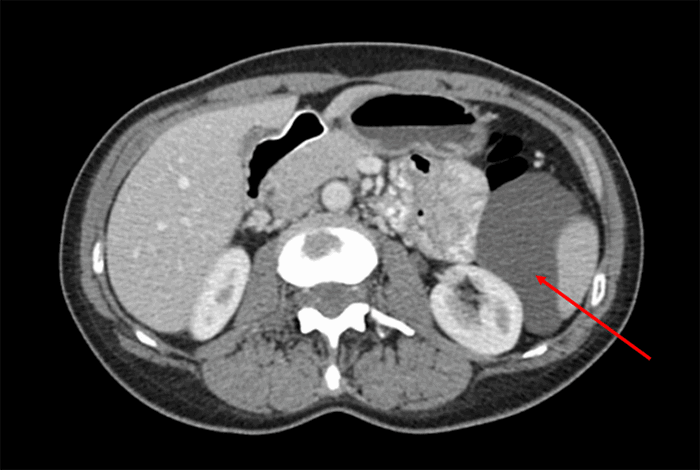

In 2014 she underwent computed tomography (CT) during her workup for pain and vaginal bleeding at an outside hospital. This imaging confirmed uterine fibroids in addition to a misidentified "left renal cyst." The cyst measured 4.8 cm × 2.9 cm and had multiple septations. Four years later, the patient had worsening abdominal discomfort and underwent workup with reimaging of her abdomen. An abdominal/pelvis CT scan (Figure 1) again demonstrated the presence of a hypodense, septate fluid collection in the left upper abdomen. The lesion had increased in size and was approximately 9.8 cm in the greatest dimension. The colonoscopic evaluation did not demonstrate any large bowel involvement. Subsequent CT-guided core needle biopsy revealed proteinaceous fluid with few inflammatory cells.

Figure 1. CT image-Axial View. Published with Permission

Hypodense fluid collection measuring approximately 84 mm in the AP dimension within the retroperitoneum abutting spleen, left kidney, pancreatic tail, and descending colon